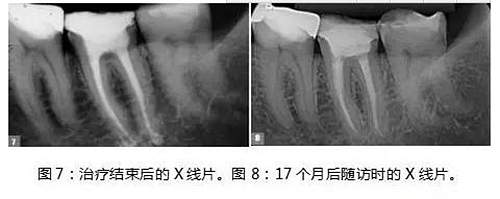

制備MTA-FILLAPEX糊劑并用主牙膠將其導(dǎo)入到根管內(nèi)(圖6)。使用攜熱器(Touch’n Heat, Kerr))除去過量的糊劑,熱垂直加壓。髓室用光固化復(fù)合樹脂密封,病人回到她的牙科醫(yī)生處,完成最終修復(fù)體的制作(圖7)。

17個(gè)月后,患者回訪, X線片結(jié)果顯示治療效果相當(dāng)成功(圖8),患者沒有陽(yáng)性的癥狀和體征,牙齒的生理功能正常,根尖位置正常,根尖周多余的MTA-FILLAPEX已經(jīng)吸收干凈了。